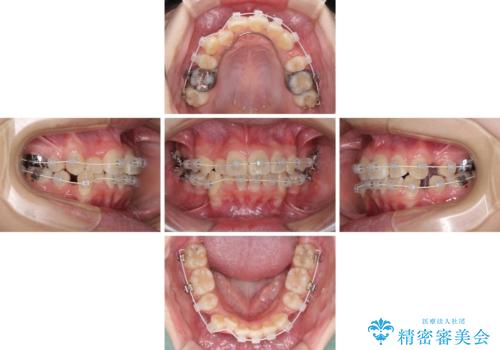

- 審美装置

- 2年2ヶ月

正中位置の改善に時間がかかることが予想され、2年半を治療期間の目標としておりましたが、20歳と年齢が若いこともあり、2年2ヶ月で治療を終えることができました。